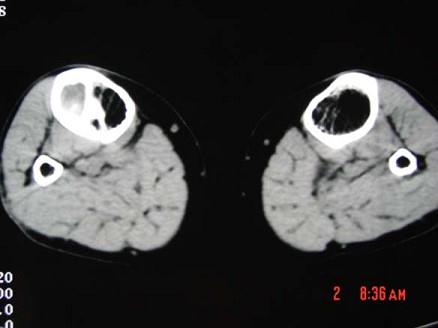

问题 患者 女,19岁,3个月前自觉右胫骨部疼痛,有轻度肿胀,请结合所提供的图像,选择最佳选項 ( )

选项 A、纤维性骨皮质缺损 B、骨样骨瘤 C、造釉细胞瘤 D、骨纤维结构不良 E、骨囊肿

答案 D